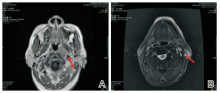

谢松喜:经科内讨论, 决定采用经皮肺穿刺活检+系统化疗+肺部手术+鼻咽部放疗的治疗方案。2013-08-01行经皮肺穿刺活检病理结果为肺浸润性腺癌。科室讨论此患者的诊断考虑为:鼻咽非角化型未分化癌伴双肺转移(cT3N1M1, Ⅳ C期), 左肺腺癌(cT1bN0M0, Ⅰ A期)。2013-08-16行第1周期TPF方案化疗(考虑本化疗方案同时对鼻咽癌及肺癌有效), 第2周期化疗后于2013-09-24复查胸部CT提示:与治疗前对比, 原发灶缩小, 转移灶减少、缩小(见图3)。治疗有效。予以继续完成共4周期TPF方案化疗。化疗结束后于2013-11-08行全胸腔镜下肺叶切除术+肺门纵隔淋巴结清扫术, 术后病理:(左下肺)肺浸润性腺癌, Ⅱ 级, 淋巴结可见癌转移(共1/9, 其中“ 段LN” 1/1)。术后恢复良好, 于2013-12-13开始行鼻咽+颈部调强放疗, 剂量66 Gy/30 F, 2014-01-23结束全程放疗。放疗后定期复查鼻咽MRI提示鼻咽肿瘤消失(见图4)。2014-07-08复查胸部CT示:左肺上叶前段结节较前增大, 考虑恶性可能性大。右肺两个小结节, 变化不大(见图5)。 此时, 我们需要明确:(1)诊断是否要改变?肺部小结节是良性或恶性?是肺多原发癌或鼻咽癌或肺癌转移?(2)左上肺新发增大的肺部结节如何处理?

图4 鼻咽MRI显示治疗前后鼻咽肿物变化情况